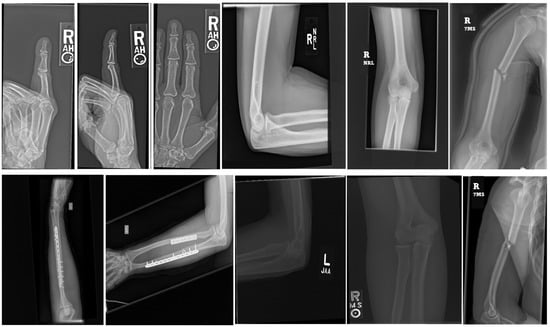

The MURA dataset [24] is the largest publicly available collection of musculoskeletal radiographic images, encompassing multi-view images of fingers, hands, wrists, forearms, elbows, humeri, and shoulders in the upper extremity region. It comprises 40,561 musculoskeletal radiographic images from 14,656 studies of 12,173 patients, with each study containing one or more radiographic images manually annotated by radiologists. This dataset is collected and released by the Stanford ML group as part of the Bone X-Ray DL Competition [24]. The training and validation sets consist of 13,457 and 1199 images, respectively, with the total number of images for each study type in the training and validation sets illustrated in Figure 1a,b.

MURA classification is a binary task with labels represented as a 0–1 variable, where 0 indicates normal and 1 indicates the presence of an abnormality. In this dataset, there are 1912 studies of the elbow, 2110 studies of the fingers, 2185 studies of the hand, 727 studies of the humerus, 1010 studies of the forearm, 3015 studies of the shoulder, and 3697 studies of the wrist. For the test set, the majority vote of three radiologists serves as the gold standard. The official team trained a baseline model using a 169-layer DenseNet to detect and localize abnormalities, achieving an AUROC of 0.929, sensitivity of 0.815 at a working point of 0.815, and specificity of 0.887. When analyzing the dataset, we observed that each study had one or more images, with most studies having three images, as exemplified in Figure 2, an illustration of the MURA. dataset.

Figure 2. Partial illustration of the MURA dataset.